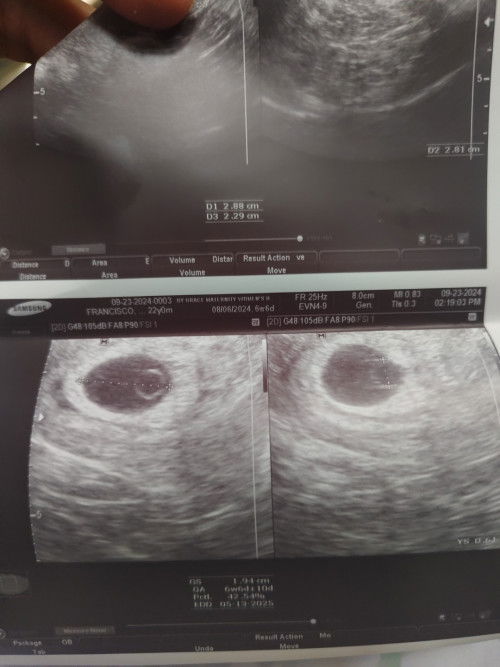

supposed to be 6w and 6d today na po kaso sabi nung ob blighted ovum daw or paconsult pa ko sa ibang ob? yan po ung ultrasound